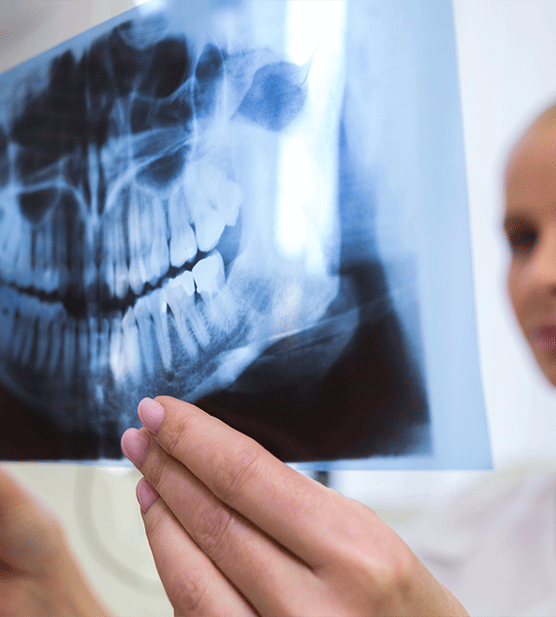

Radiografía 2D que ofrece una vista general de todos los dientes, maxilares y articulaciones. Ideal para diagnóstico inicial de ortodoncia.